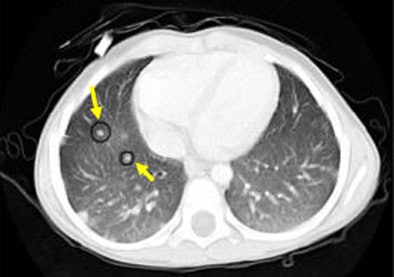

![]() |

| An example of successful nodule classification. The circle encloses a true wall nodule. The rectangle surrounds a very similar wall object that is in fact a false positive erroneously detected by the group's previous CAD system. The current hybrid FP reduction approach recognizes and removes this false-positive finding. |